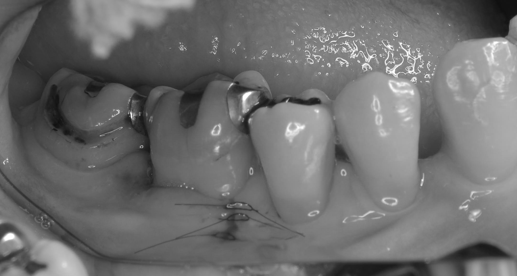

本日は左下の奥歯に大きく骨欠損をした歯を再生治療で治した症例を供覧致します。

左下の6番の遠心根が根の先の方まで骨がなくなっています。

他院で抜根(後ろの根を抜いていく治療)を勧められたとの事で来院されました・

EPPTテクニックを使い歯間乳頭を一切切らずにマイクロサージェリーを行っております。